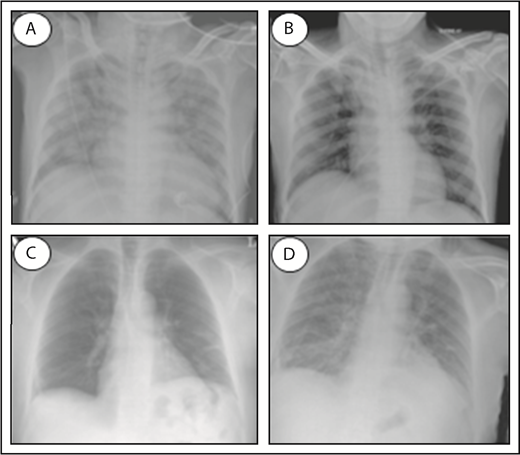

TACO and TRALI are life-threatening transfusion reactions, and it remains challenging to accurately diagnose and distinguish both syndromes. Both TACO and TRALI present with the onset of acute respiratory distress (hypoxemia) within 6 hours of a blood transfusion and demonstrate infiltrates on a frontal chest radiograph indicative of the presence of pulmonary edema (Figure 1). Clinical definitions have been established for both syndromes (Table 1). For TACO, this includes the National Healthcare Safety Network definitions published in 201624 or the 2011 International Society of Blood Transfusion (ISBT) criteria,25 whereas for the diagnosis of TRALI, the 2005 National Heart, Lung, and Blood Institute Working Group definitions26 or the 2004 Canadian Consensus Conference criteria27 are commonly used (Table 1). The clinical definitions of TACO may include evidence of positive fluid balance or cardiogenic involvement, which may manifest as left heart failure, elevated blood pressure, or tachycardia. In contrast, TRALI is strictly noncardiogenic, without evidence of left arterial hypertension, and thus, circulatory overload must be excluded. In addition, no temporal relationship to an alternative risk factor for acute lung injury (eg, pneumonia, sepsis, aspiration, multiple trauma, and acute pancreatitis) may be present for the diagnosis of TRALI; otherwise, it has to be classified as “possible TRALI.” It has been suggested that the transfusion itself may have a minor contribution in possible TRALI and that this term should therefore be replaced by “transfused acute respiratory distress syndrome (ARDS).”28,29 Others, however, argue against this by stating that Possible TRALI is a distinct clinical entity, which is especially evident in critically ill and injured patients.30 Despite the similarity in clinical presentation between TACO and TRALI, key diagnostic features have been identified that may aid in clinical diagnosis and differentiation of TACO vs TRALI (Table 2).31 Unfortunately, the tools to perform these diagnostic analyses may not be widely available. These key diagnostic features include assessment of hydrostatic pulmonary pressure (increased in TACO), protein levels in edema fluid (protein poor in TACO), response to diuretics (may occur in TACO), and cardiogenic nonlaboratory parameters, which may be impaired in TACO (eg, decreased systolic injection fraction, increased systolic blood pressure, increased vascular pedicle width, and increased cardiothoracic ratio on chest radiograph, in TACO). Increased ventricular filling or myocardial stretching may be assessed as well in the diagnosis of TACO by analyzing the levels of BNP or N-terminal pro-BNP because both have demonstrated a significant positive correlation between pre- and posttransfusion levels in TACO patients.32,33 Caution, however, is required with the use of natriuretic peptides as a diagnostic measure for distinguishing TACO from TRALI, because these levels may also be significantly increased in critically ill patients suffering from TRALI.34 Importantly, cardiac ischemia (ischemic changes on electrocardiography or increased new troponin T levels) must be excluded in diagnosing TACO. Supportive clinical and laboratory features may perhaps further help in the diagnosis of TACO or TRALI (Table 3).35 This includes physical examination of neck veins (distended in TACO), auscultation (rales, S3 in TACO), and blood pressure measurement (increased in TACO). Regarding body temperature, TRALI patients are frequently febrile, but fever may be present in one-third of TACO patients as well.36 Supportive laboratory investigations may include determination of white blood cell counts (transient leukopenia and mild thrombocytopenia in TRALI),37-40 the detection of antibodies against recipient HLA class I/II and/or human neutrophil antigen (HNA) antigens in the involved blood donor (in ∼80% of TRALI cases),41 and analysis of cytokines, as is discussed later in more detail. It remains, however, unknown if blood cell counts are affected and if antileukocyte antibodies could be present in TACO patients. Notably, there are ongoing international efforts to further define TACO, which include the 2017 ISBT working party on Haemovigilance together with the International Haemovigilance Network, which have proposed revised TACO criteria to establish a surveillance definition for reporting and tracking purposes.42

Chest radiographs of a TACO and TRALI patient. Patient at time of TACO occurrence (A), and the same patient after resolution of TACO (B). Pretransfusion patient (C), and the same patient at time of TRALI occurrence (D). Normal chest radiographs without signs of pulmonary edema (B-C); infiltrative changes indicative of pulmonary edema (A,D). Adapted from Agnihotri and Agnihotri110 and Vlaar and Juffermans22 with permission.